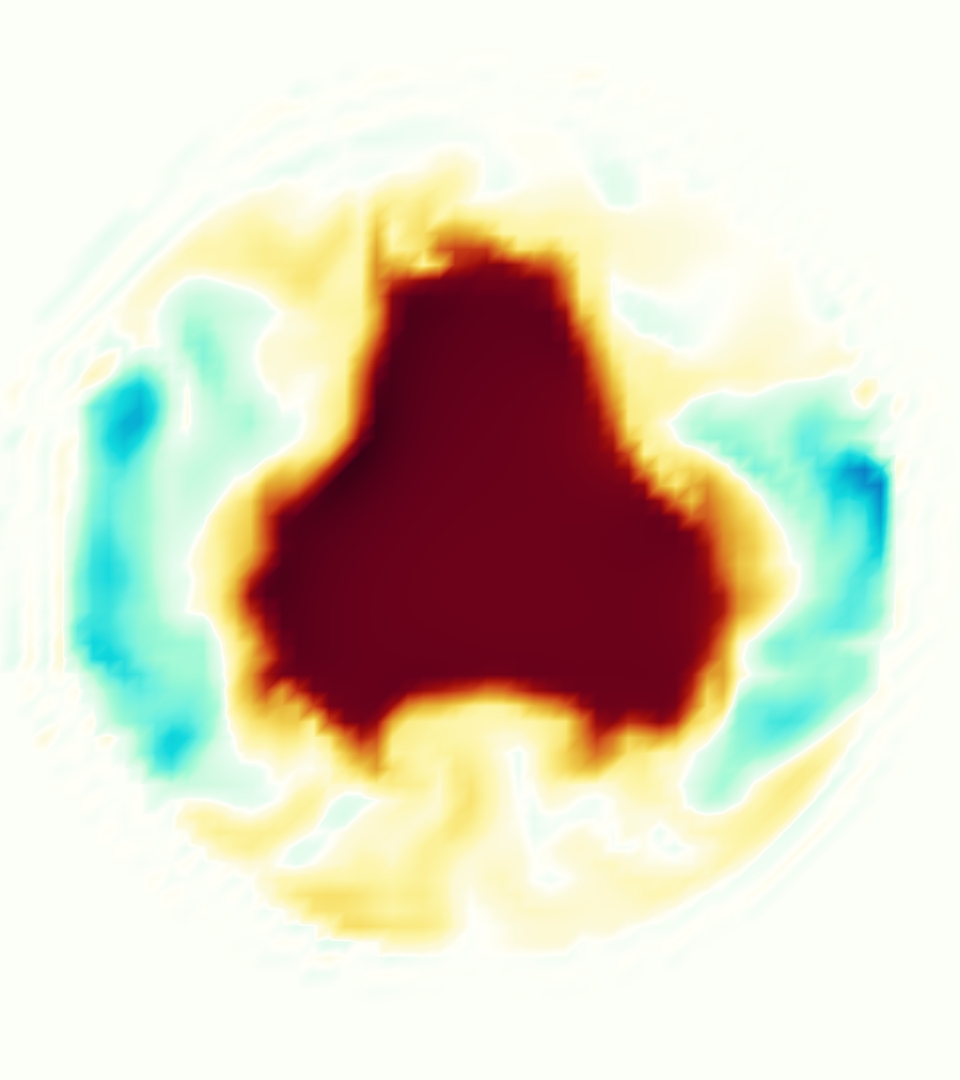

The emergent hemodynamics showed excellent qualitative agreement with experiments. Slice views of the axial component of fluid velocity ( component) in the sagittal plane that cuts through the center of the vessel, parallel to the flow direction, are shown in Figure 5. The flow in both the simulation and the experiment began to accelerate at the same time, with a jet forming through the open valve leaflets. The velocity, angle, and shape of the jet agreed well between the two cases during systole. The simulation captured the slight upward angle of the jet, which was not fully centered in the vessel. It also matched the location where the jet impacts the wall and the slower speed of the jet as it turns with the MPA downstream. As the flow decelerated, the fluid along the interior curve of the vessel reversed first while forward flow persisted where the jet was strongest, as seen in both the simulation and experimental results.

In both the experiment and the simulation, a separation region of reverse flow developed along the interior curve of the vessel under the core jet through the valve. The reverse flow began to develop at the same time in the cardiac cycle and grows throughout systole. The simulation lacked reversed flow in the entire region where reversed flow was present in the experiment, but this region developed some flow separation and had much slower flow than elsewhere in the vessel. Thus, the simulation captured that this is a distinct region from the core jet through the valve opening. There was a smaller amount of slower and slightly reversed flow along the outer curve of the vessel, close to the valve annulus and scaffold support. This region was well-matched between the experiment and the simulation.

Slice views of the (axial) component of fluid velocity in the axial plane, orthogonal to the flow direction, show that the simulation replicated the development of the jet over the cardiac cycle. At each phase, the simulation matched the forward speed of the core of the jet and the locations of reverse flow back towards the valve annulus. While there are some differences in the shape of the jet at certain phases and locations, the simulation clearly produced the general dynamics of the cardiac cycle that are seen in the experiment.

At = 0, the axial slice directly at the valve annulus shown in columns 1 and 2 in Figure 6, there was excellent agreement between the simulation and experiment over the cardiac cycle in the speed and shape of the jet through the valve. In both cases, the axial velocity increased as the flow accelerated during systole and the valve leaflets opened, then decreased during diastole with slight negative velocity before the valve leaflets were fully closed. The forward flow through the valve annulus did not form a full circle, but rather developed a triangular shape with a point of the triangle forming along the interior curve of the vessel, at the bottom of the axial slices. At = 0, the points of this triangular jet shape aligned with the commissures of the valve. This shape persisted during peak systole and was well-matched by the simulation.

The axial slice = 0.625 cm, shown in columns 3 and 4 in Figure 6, cut through the support scaffolding of the valve and the leaflets when they are open. In the experimental data, the shape of the jet changed as it moved downstream. A triangular shape occurred, but the points were then aligned with the middle of each open leaflet as opposed to the commissures. Those points were also more rounded than they were at = 0. The peak velocity of the jet was faster at = 0.625 cm than at = 0, as the flow accelerated through the open valve leaflets. The simulation produced these features at = 0.625 cm. The triangular shape of the jet shifted similarly, and its speed increased compared to the upstream slice. As the flow decelerated into diastole, the jet shape remained roughly triangular but diminished in intensity before disappearing after valve closure.

The jet continued to develop at = 1.25 cm, an axial slice immediately downstream of the valve scaffolding and open leaflets, shown in columns 5 and 6 in Figure 6. In the experimental data, the points of the triangular jet shape extended further towards the vessel wall. In addition, regions of reversed flow developed in the locations downstream of the commissures, resulting in curved sides to the shape of the jet. Each tip of the jet was unique, due to variations in the individual leaflets in the physical bioprosthetic valve. These variations are apparent in the velocity fields, possibly because the jet edges are similar enough cycle to cycle that irregularities are still being captured even with phase averaging. Further discussion of these features can be found in Schiavone et al. [39], which showed that the jet tip shapes occurred in different pulmonary anatomies, demonstrating that they were likely due to inherent properties of each leaflet. The leaflets in the mathematical model of the valve are identical, so these nuances in leaflet variation could not be replicated. The simulation did capture some of the extension of the tips of the jet, as they were closer to vessel wall at slice = 1.25 cm than = 0.625 cm. The curves in the triangular sides of the jet were also present in the simulation, though they were less pronounced than the experimental data. At both = 0.625 cm and = 1.25 cm, the jet shape in the simulation was smoother than the jet in experiment. It is possible that the free edges of the leaflets in the mathematical model are not fully replicating the behavior of the physical leaflets of the bioprosthetic valve, in particular the amplitude or frequency of leaflet flutter, leading to the variations seen in the jet shape at = 1.25 cm downstream of the leaflet edges. The simulation, however, does capture the key features of the triangular shape and speed of the jet. Overall, qualitative comparisons demonstrated that the simulation reproduced key features of the flow during systole and diastole.